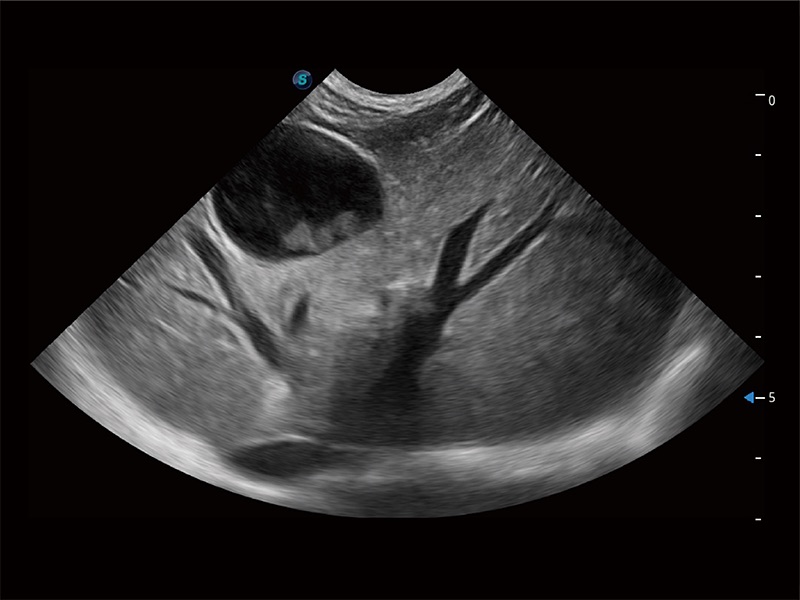

ProPet 80 全新的动物超声智能软件和丰富的探头群,为动物医生提供了高清晰度和精细分辨率的图像,无论在宠物、马科、畜牧还是实验室动物等应用中都可以轻松应对,为您的日常工作带来满意的体验。

(犬)肝脏

(犬)胎儿四腔心